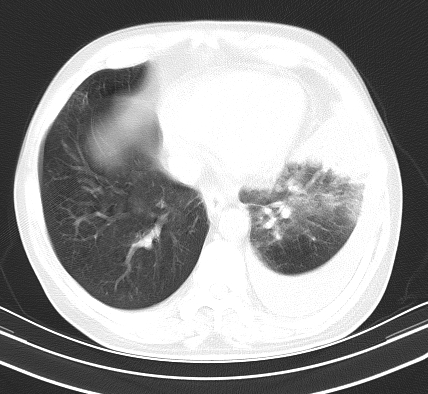

以下是引用老爱克斯新网客在2008-7-31 6:30:00的发言:[br]左肺上叶大片状病灶,左肺上叶支气管狭窄呈鼠尾状,左肺门增大,纵隔内见肿大淋巴结,左侧胸腔积液,余肺清晰。左肺中心型肺癌淋巴结转移,

以下是引用zjb在2008-7-31 6:32:00的发言:[br]左侧中心性肺癌 阻塞性肺炎 肺不张 胸腔积液 建议气管镜

以下是引用zjzjr在2008-7-31 8:45:00的发言:[br]考虑左侧中心性肺癌伴阻塞性肺炎,左肺上叶肺不张,纵隔淋巴结转移;左侧胸腔积液。建议行纤支镜检查。

以下是引用sdzyy在2008-7-31 8:47:00的发言:[br]病灶较治疗前有所进展,胸水增多, 左侧中心性肺癌 并 阻塞性肺炎 肺不张 胸腔积液 可能性大; 建议气管镜检查。 [br] [br]